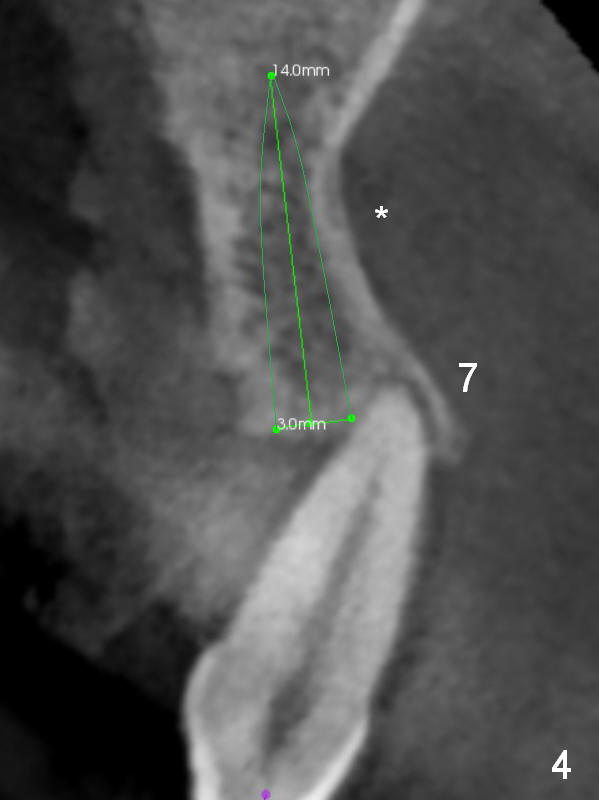

In case primary stability is questionable for example at #15 (Fig.10), consider placing implants at #12 and/or 14 (Fig.7,9).